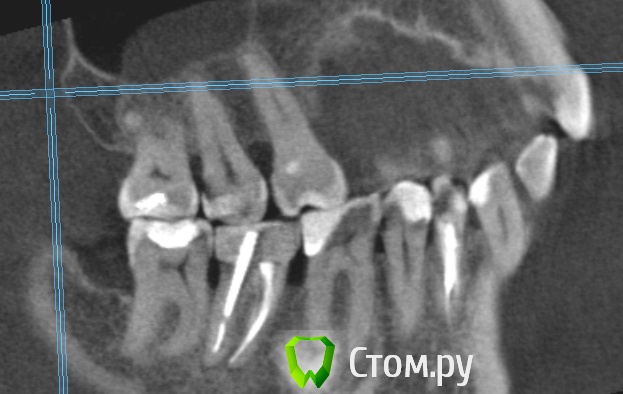

Dmitrich Опубликовано 30 сентября, 2014 Поделиться Опубликовано 30 сентября, 2014 Здравствуйте уважаемые форумчане. Вообщем такая у меня проблема, постараюсь описать менее сумбурно. Сначала я удалил 4.7 зуб из за кариеса корня. После этого примерно через неделю начались боли с другой стороны челюсти. Пришел на прием - мне по рентгену опредилили больной 3.7 (там был глубокий кариес и раза 3 переставляли пломбу на протяжении лет так 20) Его депульпировали, но боль не прошла. Сначала болело при накусывании (это нормально как я понимаю), потом просто стали ноющие боли. На месяц я уехал из города и боли были разной интенсивности. Обращался к двум разным стоматологам в отъезде - все гвоорили что это отстаточное явление после лечения. Постукивание по зубу чувствительно до сих пор. С тех пор уже 3 месяца - ноющие боли не проходят. Обращался в разные клиники, делал КТ месяц назад. Может не болеть дня 3-4 совсем, я уже обрадуюсь, на следующий день опять начинает тянуть. Утром всегда не болит, к обеду начинает. Чистили карман между 6 и 7. Результат улучшается на день-два. Ходил на прием к ортодонту, тот сказал нужно лечить 6й, состояние десен почти в норме, ко крайней мере острого воспаления нет. С КТ сделал скриншоты 6го и 7го, прикладываю. 6й зуб проверяли проводимость нерва аппаратом - результат ок )) Что мне все таки делать в данной ситуации? В клинике где лечил зуб говорят он вылечен нормально. Ссылка на комментарий

M@estro Опубликовано 30 сентября, 2014 Поделиться Опубликовано 30 сентября, 2014 Проблема в 3.6 Ссылка на комментарий

Korel Опубликовано 30 сентября, 2014 Поделиться Опубликовано 30 сентября, 2014 Проблема в 3.6 И (или) в 35 Ссылка на комментарий

Паращук Роман Опубликовано 30 сентября, 2014 Поделиться Опубликовано 30 сентября, 2014 (изменено) Или 3.6,2.7. Возможна трещина в 3.7 Изменено 30 сентября, 2014 пользователем Паращук Роман Ссылка на комментарий

Dmitrich Опубликовано 30 сентября, 2014 Автор Поделиться Опубликовано 30 сентября, 2014 Спасибо всем за советы. 2.7 сделал с месяц назад, не помогло. 3.6 получается делать точно? Странно вроде относительно недавно (года 2 назад) менял там пломбу из за того, что откололся край - вообще никаких проблем не было. Нерв проверяли - жив. То что на верхушках корня там - три месяца назад было тоже самое. А вот с трещиной вы напугали. Смотрели эту КТ несколько раз несколько стоматологов, трещину никто не увидел. Она же вроде сильно должна болеть? Ссылка на комментарий